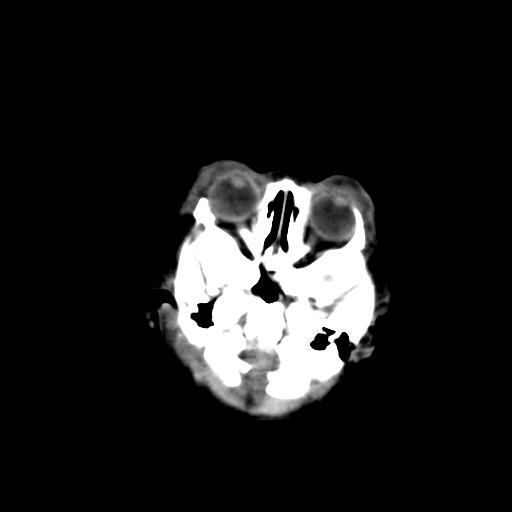

男,2天,孕31周早产儿,出生后窒息3分钟,精神反应差。

脑实质弥漫低密度,灰白质界限不清:结合临床考虑重度hie